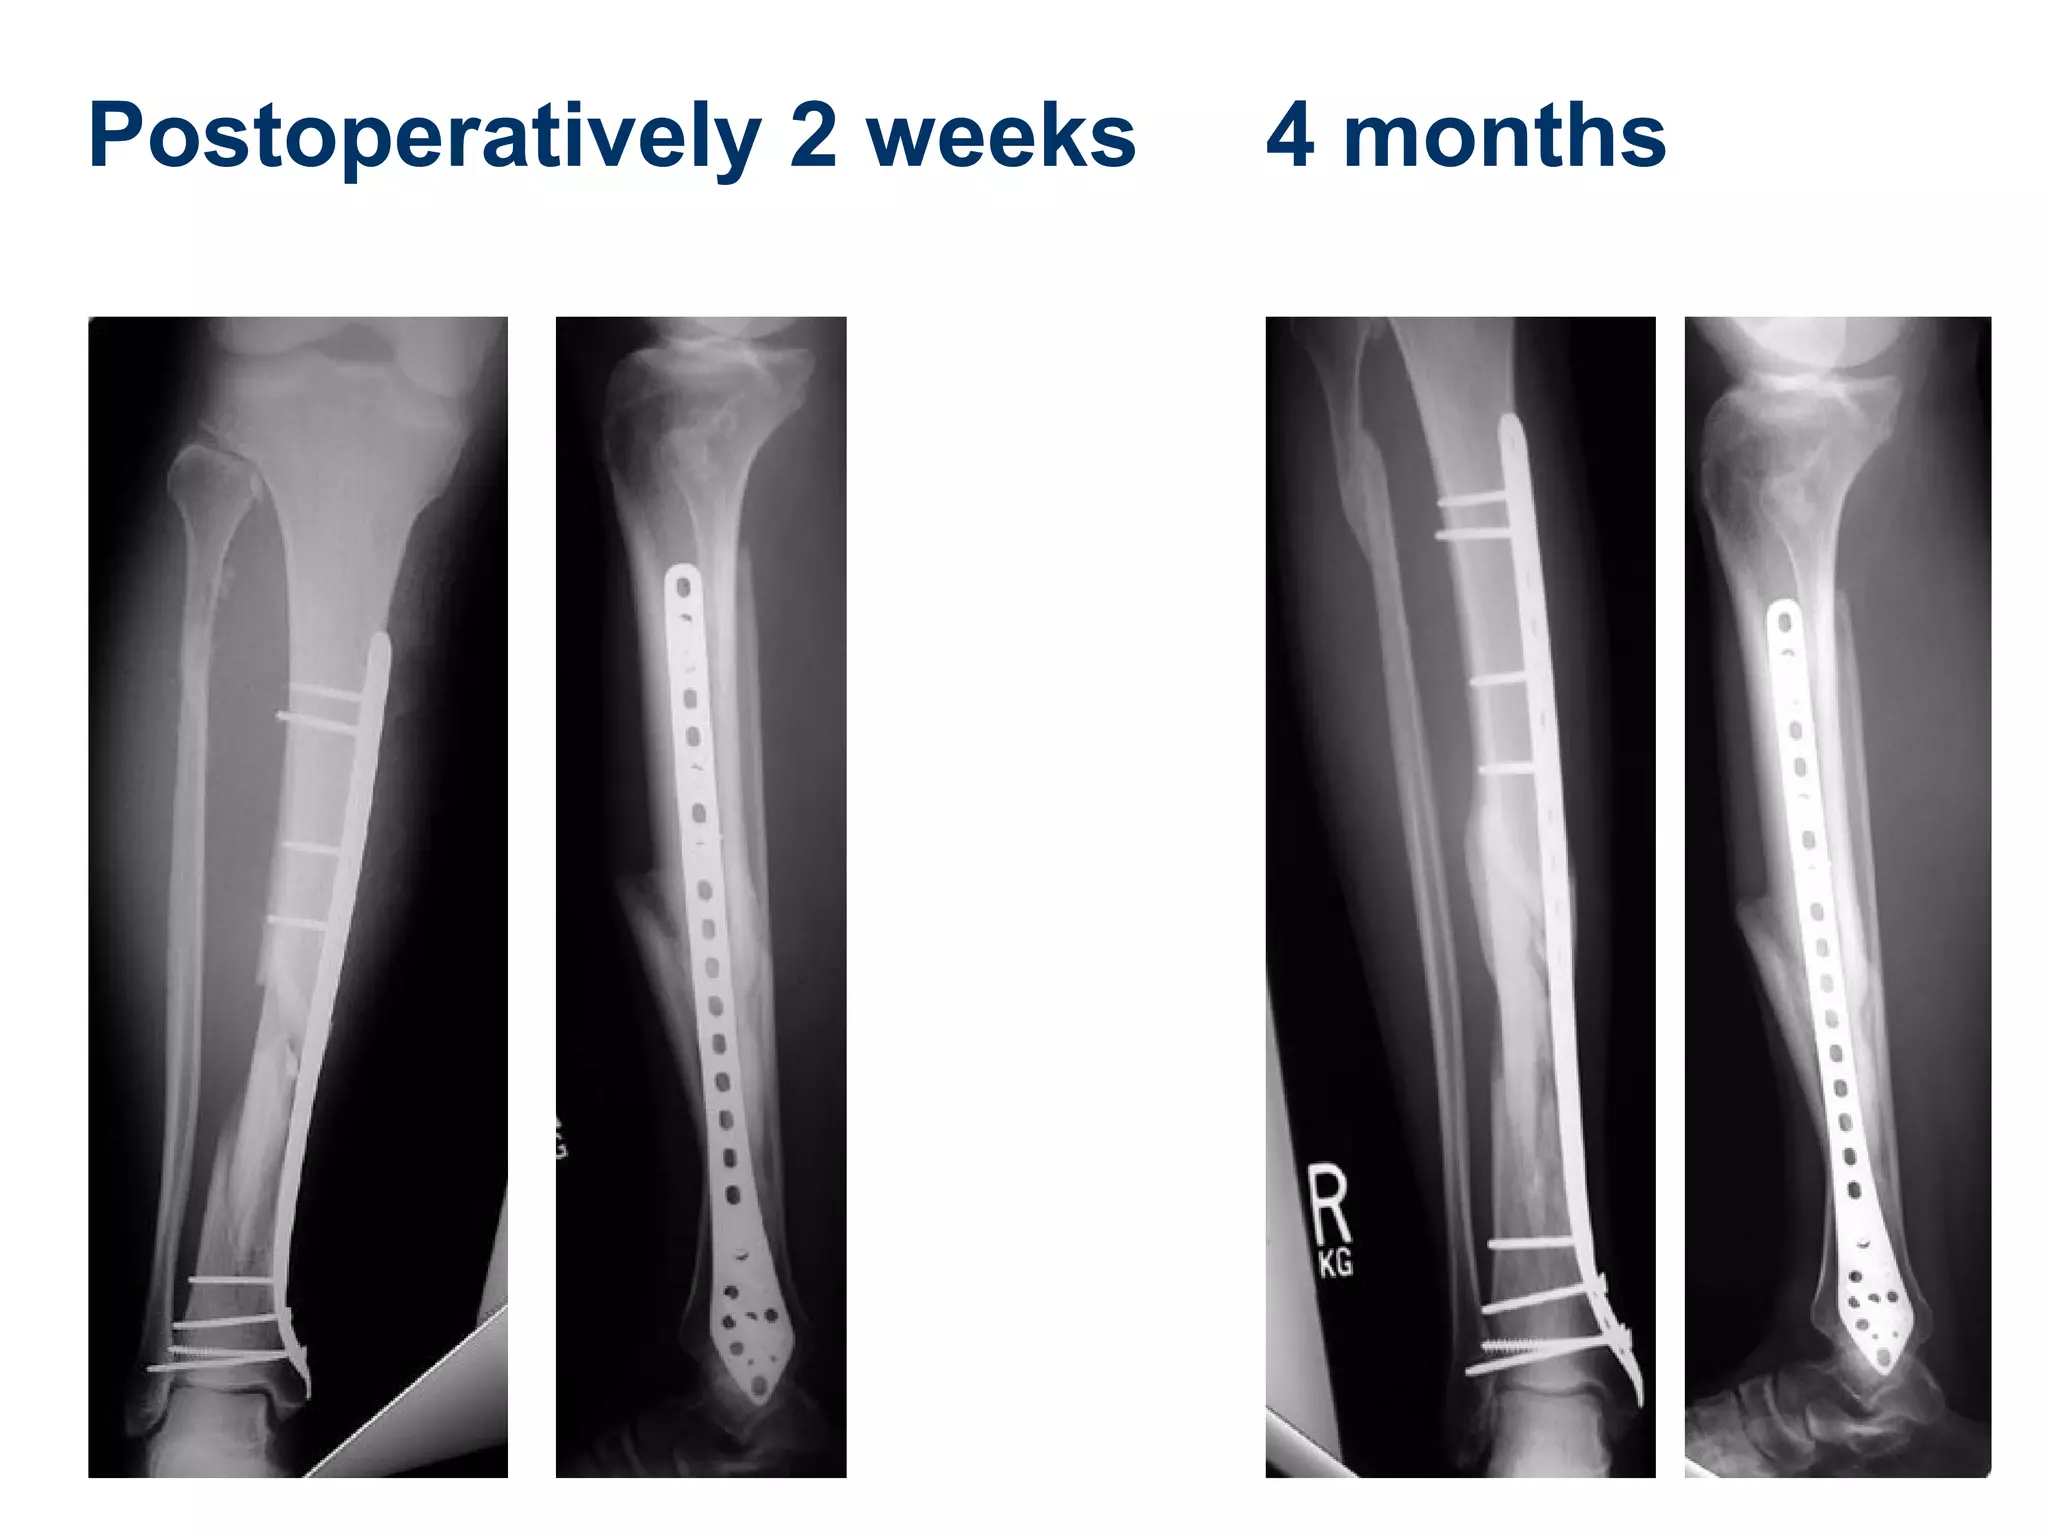

Postoperatively 2 weeks 4 months